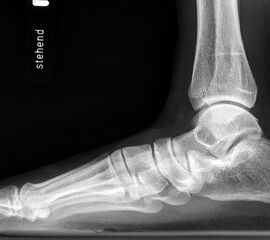

Stehende Aufnahmen des Fußes dorsoplantar (dp) und seitlich sowie des OSG anteroposterior (ap) sind die Grundlage der konventionellen Röntgendiagnostik (Abb. 5). Ergänzend werden gelegentlich die Rückfuβ-Alignement Aufnahme nach Saltzman 19 und Vergleichsaufnahmen der Gegenseite durchgeführt.

Auf der seitlichen, stehenden Aufnahme des Fußes wird ebenfalls der laterale Talo-Metatarsale I Winkel (Abb. 6 d) gemessen und so das kollabierte mediale Längsgewölbe dokumentiert. Auch hier gilt ein Talo-Metatarsale I Winkel von > 5° (nach plantar konvex) als pathologisch 21. Der Kollaps findet dabei meist im Talonaviculargelenk, seltener in der Naviculocuneiform-Gelenkreihe statt. Instabilität und Arthrose im 1. TMT sollten ausgeschlossen oder bei der Operationsplanung mit einbezogen werden. Weitere wichtige radiologische Messungen zur Beurteilung der Planovalgus-Statik und Progression der Deformität sind der laterale talo-calcaneare Winkel (Abb. 6 e) und der Abstand des Os cuneiforme-Unterrandes zum Untergrund (Abb. 6 f, Cuneiform height, 22. Eine anteriore Translation des Talus auf dem Kalkaneus findet man sowohl auf der ap, als auch auf der seitlichen Aufnahme des Fuβes mit Aufhebung der Cima-Linie.

Die stehende OSG ap -Aufnahme kann zunächst das fibulocalcaneare Impingement und im Endstadium laterale OSG Arthrose oder Valgus-Tilt des Talus zeigen.